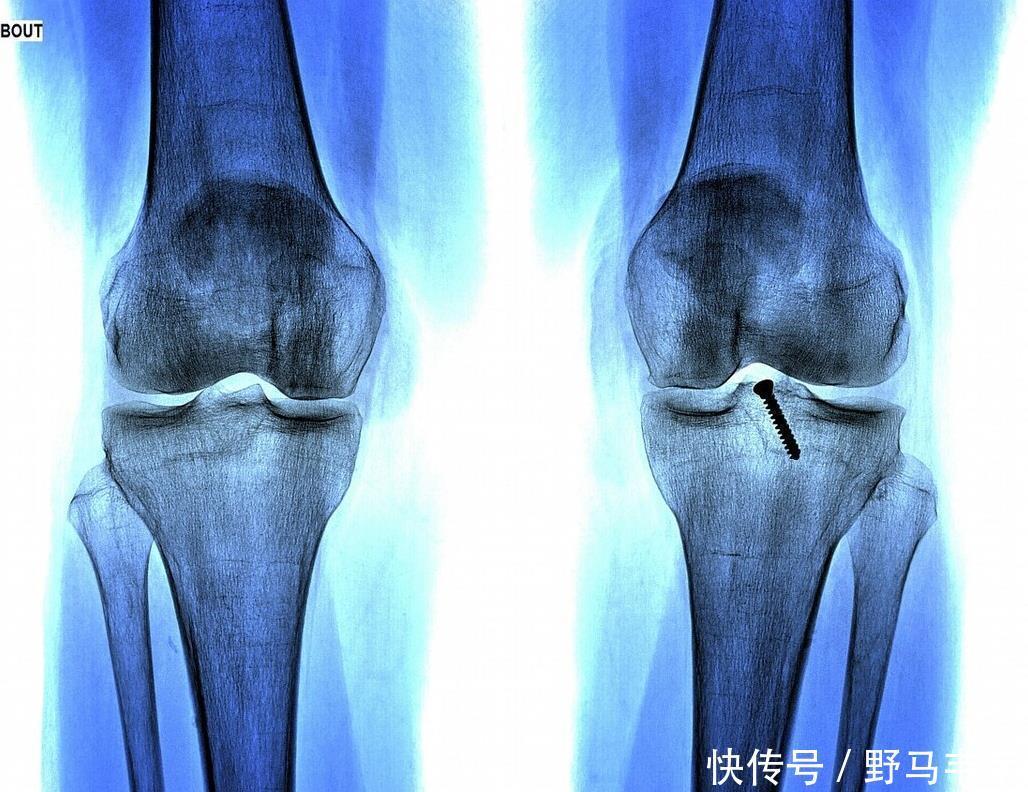

【 结果|9岁男孩骨骼线完全闭合,检查结果出来后,家长引咎自责】听到别人夸自己的儿子,庆庆父母当然开心了,也没有觉得孩子的身体会有什么问题,直到学校里组织体检,医生告知庆庆父母:孩子的骨骺线已经完全闭合了,再也不会长高了!庆庆父母心里打鼓,但是不相信,就带着孩子去大医院做了个全面检查,结果却是一样的,这让庆庆父母直接崩溃了。

检查结果出来后,根据和医生的一番交谈才知道,最终害孩子长不高的“元凶”是自己,是自己给庆庆吃的营养太丰盛,高估了孩子脾胃运化能力,提前透支了孩子的发育潜能,致使孩子骨骺线闭合,导致孩子过早停止发育。因此,给孩子好吃好喝的,并不是好事,相反,有时候可能是害了孩子。